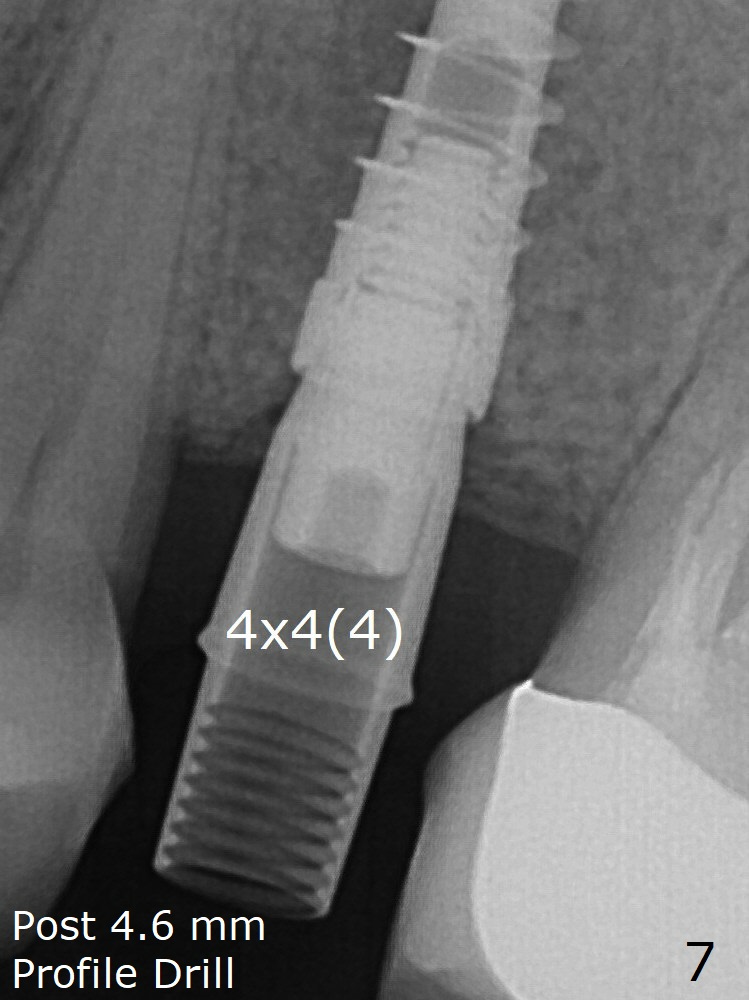

When a narrower abutment with longer cuff is placed at #15, there is no gap between the implant and abutment. In contrast there is one at #13 (Fig.6 <) when a 4x4(4) mm abutment is seated following removal of a healing abutment. After use of a 4.6 mm profile drill, the gap disappears (Fig.7). Impression is taken.